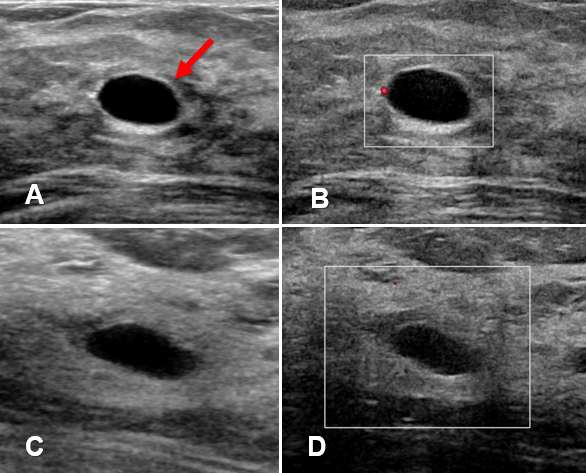

Simple Cyst

Simple breast cysts are benign, fluid-filled lesions that do not have malignant potential. Simple cysts have characteristic features on mammography and ultrasound that allow definitive diagnosis.

Ultrasound - Ultrasound is a particularly useful modality to evaluate breast cysts due to its ability to differentiate fluid-filled cysts from solid masses. Simple cysts appears as well-circumscribed, anechoic, round or oval structures, with thin walls that demonstrate posterior acoustic enhancement. Simple cysts can often be moved or compressed with the ultrasound probe which can help distinguish cysts from solid masses, which are usually immobile. Additionally, simple cysts do not exhibit vascularity nor contain internal echoes or solid components.